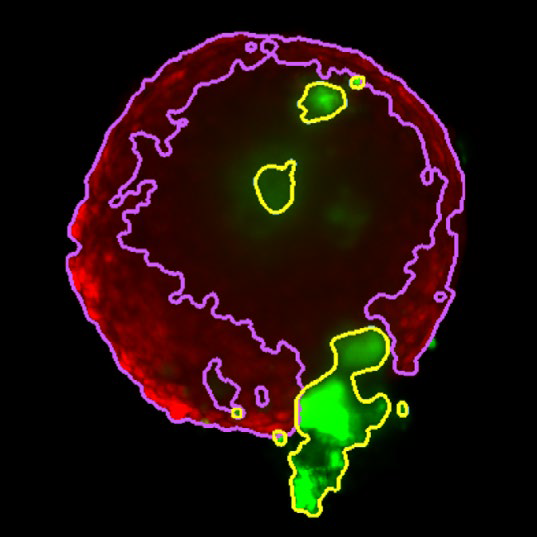

Z slice of the tumor microtissue treated with 0.05% DMSO - tumor (yellow region) and fibroblast (purple region) are recognized separately in 3D

Figure 3. Z slice of the tumor microtissue treated with 0.05 % DMSO - tumor (yellow region) and fibroblast (purple region) are recognized separately in 3D. Image Credit: Yokogawa Life Science

Z slice of the tumor microtissue treated with 5 μM Lapatinib - tumor (yellow region) is decreased significantly comparing to the one treated with 0.005% DMSO

Figure 4. Z slice of the tumor microtissue treated with 5 μM Lapatinib - tumor (yellow region) is decreased significantly compared to the one treated with 0.005 % DMSO. Image Credit: Yokogawa Life Science

Tumor spheroids were created by seeding an Akura 384 plate with a monodispersed mixture of GFP-expressing NCI-N87 (gastric carcinoma) and RFP-expressing NIH3T3-L1 (murine fibroblast) cells, which spontaneously formed spheroids through scaffold-free self-assembly over several days. After spheroid formation, selected wells containing tumor spheroids were treated with DMSO at 0.05, 0.5, or 5.0 μM Lapatinib for six days. The images were analyzed in 3D, with NCI-N87-GFP (tumor) and NIH-RFP (fibroblast) identified separately, and the volume of each spheroid measured.

This research allowed InSphero AG to accurately quantify pharmacological effects on their 3D models. The fully automated system enhanced multi-condition simultaneous testing, leading to increased workflow efficiency. By implementing the HCA platform, InSphero AG provides seamless solutions, from in vitro 3D models to evaluations.

The volume of NCI-N87-GPF (tumor) decreased significantly in a concentration-dependent manner with the addition of Lapatinib

Figure 5. The volume of NCI-N87-GPF (tumor) decreased significantly in a concentration-dependent manner with the addition of Lapatinib. Image Credit: Yokogawa Life Science